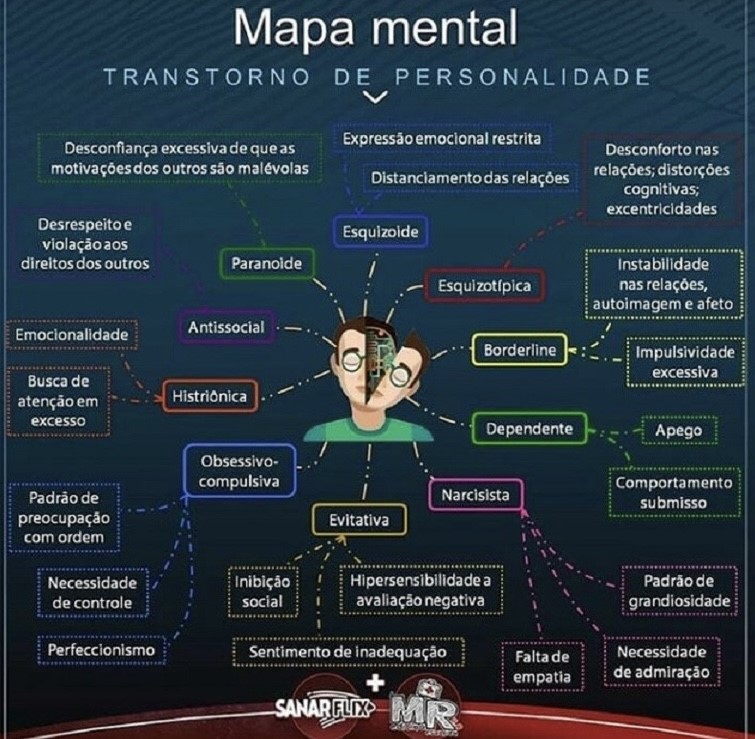

O diagnóstico desses transtornos deve ser feito pelo psicólogo ou psiquiatra, onde é observado um padrão persistente na experiencia interna e no comportamento que se desvia acentuadamente da expectativa da sua cultura. Se manifestando na área cognitiva (por exemplo na forma de perceber e interpretar a si mesmo, outras pessoas, assim como eventos), na área da afetividade (como por exemplo na variação da labilidade, intensidade e adequação da resposta emocional), no funcionamento interpessoal e controle dos impulsos. Causando um sofrimento psíquico, social e profissional significativo. Normalmente, o surgimento ocorre a partir da adolescência e início da fase adulta. Sendo que para um transtorno de personalidade ser diagnosticado corretamente, a um indivíduo com menos de 18 anos de idade, as características precisam estar presente por pelo menos um ano. Isso porque, os traços de personalidade que surgem na infância, com frequência não persistem com mudança na vida adulta, sendo a única exceção é o transtorno de personalidade antissocial que não pode ser diagnosticado em pessoas com menos de 18 anos. E o seu tratamento consiste na realização de sessões de psicoterapia e, em alguns casos, uso de medicamentos, receitados pelo médico. Eles são distribuídos pelo DSM V em três grupos: o Grupo A que inclui transtorno de personalidade Paranoide, Esquizoide e Esquizotípica. Pessoas com esse tipo de transtornos frequentemente parecem ser “esquisitos” ou “excêntricos”. O Grupo B que inclui os transtornos de personalidades Antissocial, Borderline, Histriônica e Narcisista, onde os indivíduos com esse transtorno parecem ser “dramáticos”, “imprevisíveis” ou “emotivos”. E o Grupo C inclui os transtornos de personalidade Evitativas, Dependentes e Obsessiva-compulsiva, no qual as pessoas com esse transtorno com frequência parecem ser “ansiosas” ou “medrosas”. Podendo observar um único indivíduo com transtornos de grupos diferentes. Os dez principais transtornos de personalidade são:

Personalidade narcisista

Caracterizado por uma supervalorização e sentimento grandioso acerca de si próprio, além de uma grande necessidade de reconhecimento e desvalorização de outras pessoas. Os narcisistas são egocêntricos e acreditam que são especiais, únicos e superiores às outras pessoas, sentem que devem ser admirados e tratados de forma especial por parte dos outros, tiram vantagem das outras pessoas para atingir os seus próprios objetivos, têm falta de empatia e não entendem os sentimentos e necessidades dos outros, sentindo frequentemente inveja ou acreditam ser alvo da inveja alheia.

Personalidade Borderline

O transtorno de personalidade borderline, ou síndrome de borderline, caracteriza-se por uma instabilidade nos relacionamentos interpessoais e por sentimentos constantes de vazio, alterações repentinas de humor e acentuada impulsividade. Geralmente, a pessoa com esse tipo de transtorno de personalidade faz um grande esforço no sentido de evitar o abandono, tem um padrão de relacionamentos instáveis e intensos, avaliando as pessoas como boas em um instante e rapidamente as julgando como más. Além disso, em alguns casos, pode apresentar comportamentos de automutilação ou ameaças suicidas.

3.Personalidade Antissocial

O transtorno de personalidade antissocial, também conhecido como sociopatia, pode surgir muito cedo, ainda na infância, e caracteriza-se por atitudes de desrespeito e violação dos direitos das outras pessoas, descaso e desconsideração pelo certo e errado, comportamentos perigosos e/ou criminosos e incapacidade de se adequar às normas sociais. Geralmente, a pessoa com transtorno de personalidade antissocial apresenta uma grande aptidão para enganar, mentir ou iludir as outras pessoas, para obter vantagens pessoais ou prazer. Além disso, é impulsiva e agressiva e recorre muitas vezes a agressões físicas e desrespeito pelos outros, sem sentir remorso e mostrando-se indiferente por ter ferido ou maltratado alguém

4. Personalidade Evitativa

O transtorno de personalidade evitativa, também chamada de “esquiva”, caracteriza-se por uma timidez excessiva e esquiva de situações e interações sociais, com sentimentos de inadequação e grande sensibilidade à avaliação negativa por parte das outras pessoas. A pessoa com esse tipo de transtorno de personalidade geralmente evita realizar atividades interpessoais, devido ao medo da crítica e rejeição ou desaprovação, tem medo de se envolver em relacionamentos íntimos ou conhecer pessoas novas e sente-se inferior em relação ao outro.

5. Personalidade Obsessiva-compulsiva

O transtorno de personalidade obsessiva-compulsiva, é caracterizado por dois tipos de comportamento: as obsessões, que são pensamentos impróprios ou desagradáveis, recorrentes e persistentes; e as compulsões, que são comportamentos ou atos mentais repetitivos, como lavar as mãos frequentemente por medo de se contaminar com vírus ou bactérias, organizar objetos ou verificar fechaduras várias vezes, por exemplo.

6. Personalidade Paranoide

Caracterizado por uma desconfiança excessiva e suspeita em relação aos outros, em que as suas intenções são constantemente interpretadas como maldosas. Este transtorno geralmente surge no início da idade adulta, podendo ser consequência de fatores hereditários e vivências da infância. Normalmente, a pessoa não confia e suspeita de outras pessoas, sentindo frequentemente que está sendo enganado mesmo que não existam motivos. Por isso, é comum questionar constantemente a lealdade de amigos e colegas, não confiar nos outros e sentir que as suas intenções têm um caráter humilhante ou ameaçador.

7. Personalidade Esquizoide

É um tipo mais raro de transtorno de personalidade, ocorrendo com mais frequência em homens, e é caracterizado por uma tendência da pessoa se distanciar dos outros e evitar relações sociais ou relacionamentos íntimos.

Geralmente, a pessoa com esse tipo de transtorno é desapegada, indiferente e tem uma tendência a ser mais introspectiva e a fantasiar as coisas. Além disso, prefere realizar atividades solitárias, evita o contacto íntimo e social, não tem amigos íntimos, mostra-se indiferente a elogios ou críticas e é emocionalmente frio e distanciado.

8. Personalidade Esquizotípica

Normalmente a pessoa com transtorno de personalidade esquizotípica tem um comportamento, fala e aparência excêntricos, crença bizarras, que não estão de acordo com as normas culturais em que a pessoa está inserida e pensamento, percepções e discurso incomuns, semelhantes à esquizofrenia.

9. Personalidade histriônica

O transtorno de personalidade histriônica caracteriza-se por uma auto-estima baixa, sensibilidade à crítica e rejeição, e tendência a depender da atenção e aprovação de outras pessoas para o próprio bem estar. Além de usar a aparência física para chamar a atenção e usa um discurso excessivamente impressionista e expressões emocionais exageradas. No entanto, a pessoa com que tem personalidade histriônica, é facilmente influenciada pelos outros ou pelas circunstâncias e considera os relacionamentos com as pessoas mais íntimos do que realmente são.

10. Personalidade Dependente

O transtorno de personalidade dependente caracteriza-se por uma falta de autoconfiança, visão limitada de si e dos outros e pela necessidade excessiva de ser cuidado, levando a um comportamento submisso e ao medo da separação e do abandono. Além disso, a pessoa com personalidade dependente sente dificuldade para iniciar projetos ou fazer coisas por conta própria, por falta de autoconfiança, energia ou motivação. Tem ainda uma necessidade extrema de receber carinho e apoio, e sente desconforto ou desamparo quando está só. Por isso, busca urgentemente um novo relacionamento como fonte de carinho e amparo, quando o atual termina.